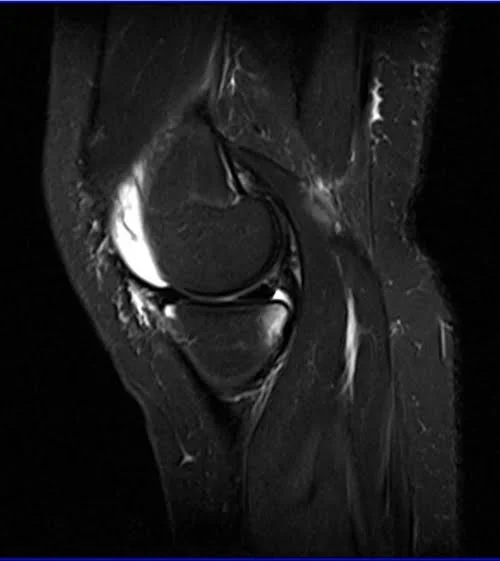

MRI knee sagittal stir 1 - MRI